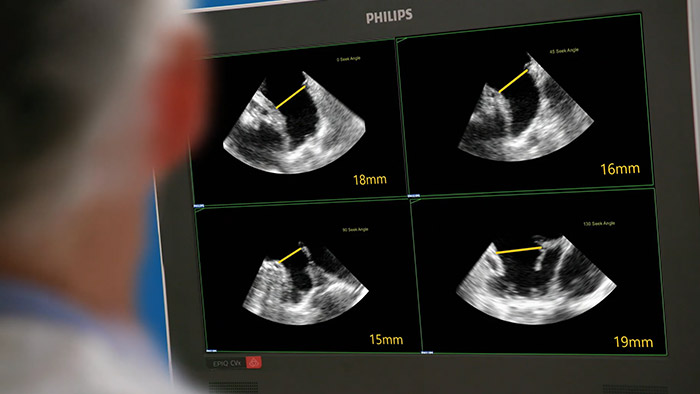

Avaliação rápida, fácil e intuitiva do apêndice atrial esquerdo. A solução LAA da Philips no EPIQ CVxi.